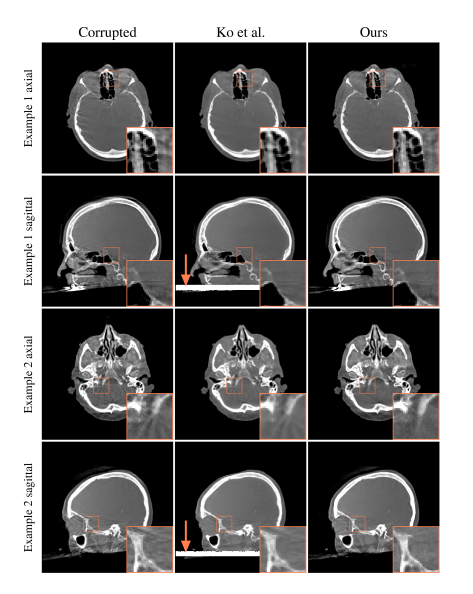

Figure 9 presents qualitative reconstructions for two example patients using real motion-affected clinical cone-beam CT scans. For each patient, an axial slice is displayed in the upper row and a sagittal slice in the lower row, both passing through the examined volume. A ×3 magnification of a region of interest is incorporated into the visualization.

图9:两个病例患者的准确运动轨迹对临床锥束CT扫描的质量有着重要影响。对于每位患者,在显示截面中分别采用轴向切片和矢状切片进行观察,并通过×3倍放大图清晰展示感兴趣区域的细节信息。

_Fig. 10: A comparison between the recovered motion patterns of clinical examples 1 and 2 in Fig. 9 to their corresponding observable motions in projection images. The upper plots represent the vertical pixel positions of anatomical landmarks identified via manual annotation in these projection images. The lower row illustrates the recovered motion curves, which include rotations and translations. The motion parameter exhibiting the highest amplitude is emphasized in orange, specifically rx for example 1 and tz for example 2.

比较图9中临床案例1(左侧)和案例2(右侧)所呈现的投影图像中的运动模式恢复情况。上部图表展示了通过手动标注确定的解剖标志在其投影图像中的垂直像素坐标位置。下部绘出了各案例恢复后的旋转和平移运动轨迹,并用橙色线条突出显示具有最大的幅值变化程度的部分:其中案例1对应于rx轴旋转轴线的变化趋势,案例2则对应于tz轴平移方向的最大位移量测量结果。各病例对应的解剖标志在其投影图像上的移动轨迹与各自最大幅值变化趋势的高度吻合